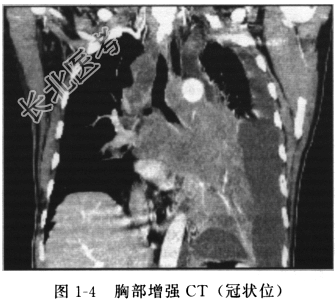

患者老年男性,因咳嗽、痰中带血、发热入院,既往吸烟多年。入院后增强CT(图1-3、图1-4)示:左肺门见不规则软组织影(大于7cm),多个纵隔淋巴结肿大,左侧胸腔积液。头颅MRI、腹部超声及全身骨ECT未见明显异常。肿瘤标志物NSE升高。胸腔积液细胞学检查,连续3次找到小细胞癌细胞。